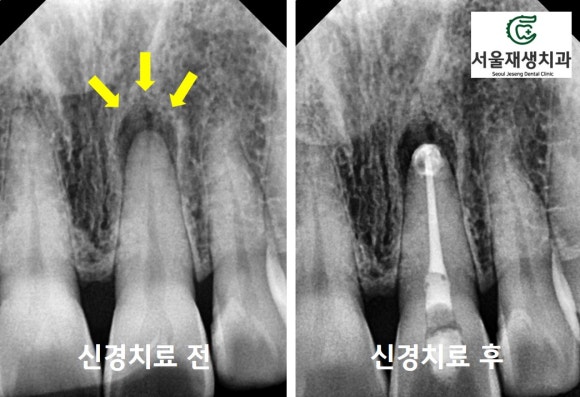

즉시 신경치료를 시작합니다!

신경치료란,

죽은 신경을 살려내는 것이 아닌,

죽은 신경 조직을 청소하는 것을 의미합니다.

치아 뒷면에 작은 구멍을 뚫고,

치아 내부로 들어가

죽은 조직들을 걷어내고 소독합니다.

이미 신경은 죽었기 때문에

이 과정에 통증은 전혀 없습니다.

신경치료가 마무리되었습니다.

신경이 들어있던 빈 공간을

깨끗히 청소하고,

빈틈없이 밀봉합니다.